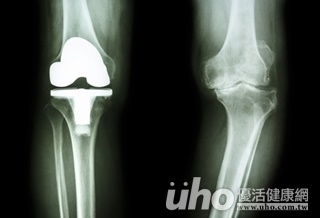

(優活健康網記者徐平/綜合報導)好神奇,導航竟可帶路換關節!苗栗一位76歲的許奶奶,因右腳關節退化,到醫院接受治療,X光檢查顯示關節磨損嚴重,內側也長出骨刺,但許奶奶因堅持不肯接受開刀時須輸血的狀況,醫師使用「電腦導航人工關節置換手術」,不但大幅減少手術時的出血量,更因電腦導航的精準定位,增加人工關節的耐用度。傳統置換手術需使用探針進入骨髓腔大千綜合醫院骨科醫師容志雄表示,傳統人工關節置換手術需使用探針進入骨髓腔,此時會經過大腿骨與脛骨2個人體最大的骨頭,造成較多出血,加上術後會放置流管3~4天,導出活動時造成的少量出血。精準抓出關節軸心、減少流血量平均一個關節手術的出血量約為500~600c.c.左右,若遇到曾有抗凝血治療或關節變形較嚴重的患者,有時出血量可能會到1100~1200c.c.,然而經由電腦導航的人工關節置換術,不需經過探針入骨髓腔能精準抓出關節軸心,可減少流血量,電腦導航人工關節置換手術的好處包含:1) 精準抓出關節軸心/容志雄醫師表示手術後關節是否能用得久,除了有無使用耐磨損的墊片之外,另外就是軸心有沒有抓得準確、是否符合人體工學,有些患者因受傷影響,關節變形嚴重,若以傳統探針方式抓軸就會非常不容易,反之使用電腦導航的定位模式,即可精準抓出軸心。2) 減少出血量/對於凝血功能差或關節變形較嚴重,甚至同許奶奶一樣有宗教因素而不願接受輸血的患者,即可不用擔心出血量過多的問題。3) 降低傳染病風險/因為出血量少,故不需輸血,就可降低因輸血造成的傳染可能性。